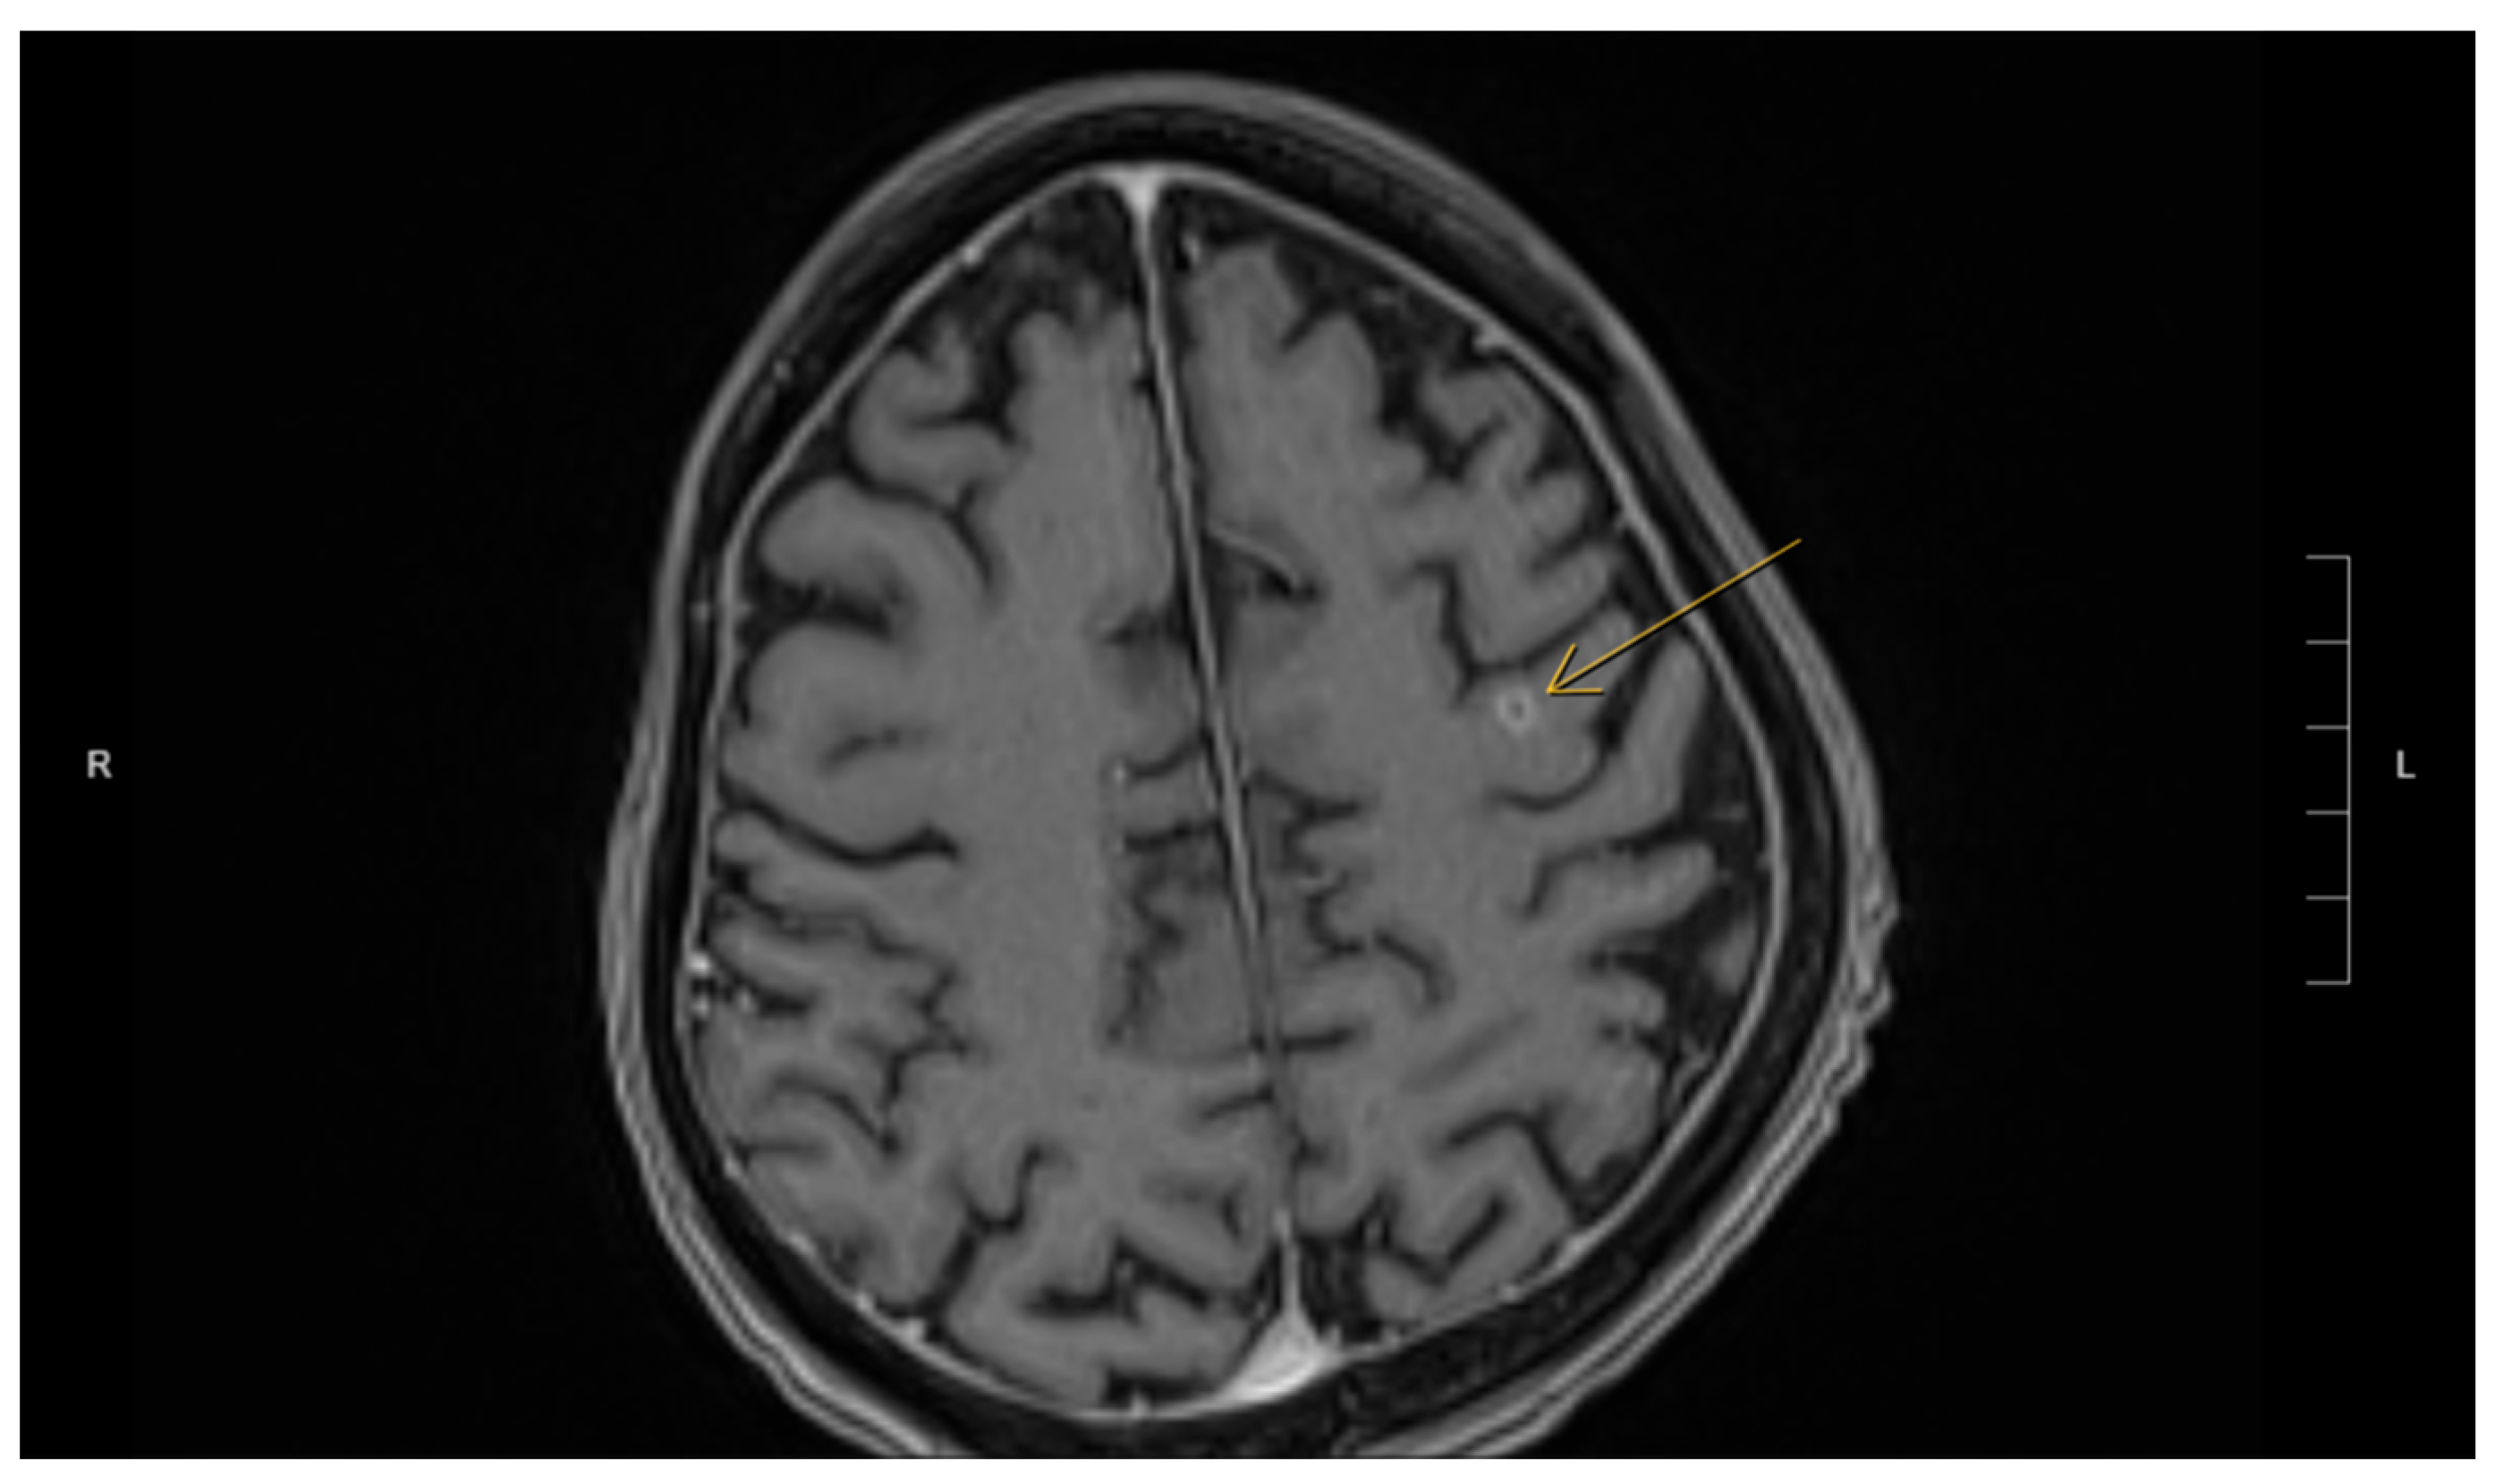

Fortunately, the histopathological examination of the targeted liver biopsy revealed necrotizing granulomas containing filamentous microorganisms. The histomorphology findings and special stain patterns raised the possibility of Nocardia infection; however, there was no reliable way to identify the specific species. The beaded morphology seen on special stains, along with the weak FITE stain signal, were consistent with features typically associated with Nocardia (see Figure 1). At the same time, Actinomyces was considered less likely due to the patient’s poor clinical response to initial antibiotic treatment with amoxicillin–clavulanate, vancomycin, and piperacillin–tazobactam, which were provided for cholangitis and possible pyogenic liver abscess. No organisms were detected on Ziehl–Neelsen staining, but the possibility of superimposed mycobacterial infection, such as TB, could not be entirely excluded due to the limited sensitivity of the Ziehl–Neelsen stain. As a result, the sample was sent for polymerase chain reaction (PCR) testing for tuberculosis, which was negative. Brain imaging was suggested to rule out a central nervous system (CNS) abscess, as CNS involvement is more common in immunocompromised patients with Nocardia infection [8]. This demonstrated a 5 mm rim-enhancing lesion in the left pre-frontal gyrus (see Figure 2). The patient was presumptively diagnosed with disseminated nocardiosis. He was initiated on antimicrobial therapy with a combination of imipenem–cilastatin and trimethoprim–sulfamethoxazole (TMP-SMX). He completed 3 months of combination therapy and thereafter was transitioned to monotherapy with TMP-SMX, which he took for an additional 5 months (total 8 months of therapy). This was discontinued at 8 months due to the development of drug-induced liver injury. While receiving this antimicrobial regimen, he demonstrated clinical improvement and radiological resolution of his brain, lung, liver, and pancreatic lesions, clinically confirming the diagnosis. He has been followed in the outpatient Infectious Diseases clinic, and one year after the discontinuation of his antimicrobials, there have been no clinical nor radiographic concerns for relapse. Figure 3 shows the timeline of the patient’s 3-month hospitalization with some selected important events.

Figure 2. MRI of the brain demonstrating a 5 mm ring-enhancing lesion (indicated by arrow) in the left precentral gyrus.